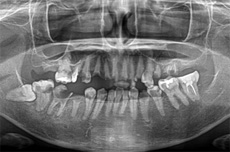

オールオン4の治療例:1

治療前

治療後